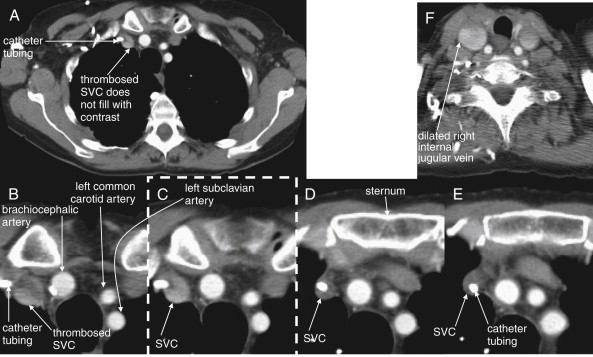

- 28.Bhatia V., Kachru R., Parida A.K., Kaul U. Twiddler’s syndrome. Int J Cardiol. 2007;116:e82. doi: 10.1016/j.ijcard.2006.08.013. [DOI] [PubMed] [Google Scholar]